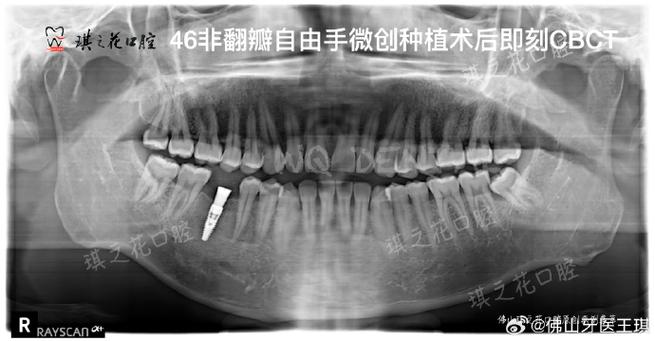

- 骨量评估:准确测量牙槽骨的高度、厚度和长度,判断是否满足种植体植入的最低要求(通常种植体长度需8-10mm,直径3.5-5mm,骨厚度需至少1mm以上),若骨量不足,需提前进行植骨增量,否则可能导致种植体松动、脱落。

- 解剖结构定位:清晰显示下牙槽神经管、上颌窦、颏孔等重要解剖结构的位置与走行,下颌后牙区种植时,若种植体误入下牙槽神经管,可能造成下唇麻木等神经损伤;上颌后牙区种植时,若穿透上颌窦底,可能引发上颌窦炎,甚至导致种植体感染失败。

- 骨密度分析:骨密度直接影响种植体的初期稳定性,CBCT可通过灰度值评估骨密度(如D1-D4类骨),医生据此选择合适的种植体类型(如亲水性种植体适用于低密度骨),并调整植入扭矩,避免因骨密度过低导致种植体骨结合失败。

- 邻牙及软组织观察:了解邻牙牙根是否倾斜、有无根尖病变,以及牙龈厚度、附着龈宽度等,为种植体植入位置、角度设计提供依据,避免损伤邻牙或影响后期修复的美观与功能。